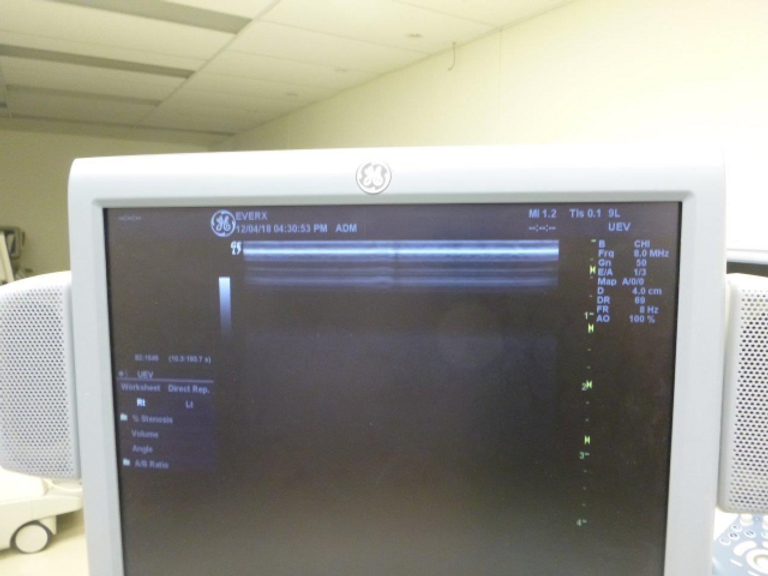

- Advanced Imaging Capabilities: Experience unparalleled image clarity and precision with the Logiq 7’s 3D technology and a comprehensive suite of imaging features, including Power Doppler Imaging, M-Mode, and Color Flow Mode (CFM).

- Wide Range of Clinical Applications: From abdominal and OB/GYN to small parts, pediatric, vascular, and cardiac diagnostic testing, the Logiq 7 supports a full spectrum of clinical applications, making it a versatile solution for diverse healthcare settings.